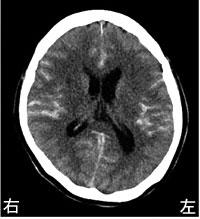

65歳の男性。右利き。突然の意識消失のため救急搬入された。診察時のJCSⅢ-200、血圧210/120 mmHg、脈拍90/分であった。搬送時の頭部CTを示す。意識を回復した際に認められるのはどれか。2つ選べ。

1

左半側空間無視

2

右上肢麻痺

3

左下肢失調

4

相貌失認

5

失語症